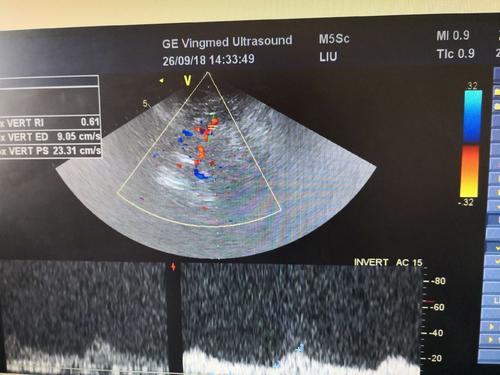

經(jīng)顱彩色編碼雙功能超聲TCCD成像模式分析

經(jīng)顱彩色編碼雙功能超聲,區(qū)別于經(jīng)顱多普勒超聲,它的英文簡(jiǎn)稱(chēng)是TCCD,后者是TCD。TCCD成像模式是什么樣的,tcd廠家澳思泰今天來(lái)分析這一問(wèn)題。

(1)依據(jù)多普勒頻移值編碼成像即f-TCCD:

依賴(lài)運(yùn)動(dòng)紅細(xì)胞所產(chǎn)生的多普勒頻移值進(jìn)行計(jì)算機(jī)編碼,可以顯示血流方向和測(cè)算血流速度,需要校正多普勒取樣角度,角度及篩查深度依賴(lài)性較大,較易產(chǎn)生運(yùn)動(dòng)偽像。

(2)依據(jù)運(yùn)動(dòng)紅細(xì)胞所產(chǎn)生的總能量進(jìn)行編碼成像即p-TCCD:

只與運(yùn)動(dòng)紅細(xì)胞所產(chǎn)生的總能量有關(guān),無(wú)需校正多普勒取樣角度,對(duì)于受取樣角度影響較大血管病變,諸如大腦后動(dòng)脈(PCA),大腦中動(dòng)脈(MCA)M2段,大腦前動(dòng)脈(ACA)A1段有一定的幫助作用,信噪比更高,不易產(chǎn)生混疊效應(yīng)。p-TCCD相對(duì)f-TCCD而言,缺點(diǎn)是不能顯示血流方向,對(duì)顯示狹窄處高速血流敏感性較低。